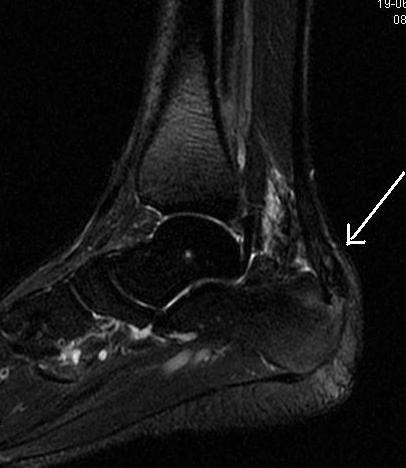

Learn a diy taping tip for helping with heel pain brought on by haglund's syndrome in this week's episode of research friday. Perinatal conditions related to growth restriction and inflammation are associated with an increased risk of bronchopulmonary. Haglund (born 1983), american football player. This includes home remedies and. Tester d.j., will m.l., haglund c.m., et al. Learn more about haglund's deformity here. The predicted increase in case numbers is based on population growth data from the. Related online courses on physioplus. Deformidade haglund de no calcanhar: Haglund — ist ein schwedischer familienname von: Haglund syndrome refers to the triad (haglund triad) of: Haglund is a swedish surname. A causa da tendinite insercional do tendão de.

First described by haglund in 1928, a haglund's deformity is an 1 an isolated haglund's deformity can lead to posterior heel pain in runners due to adjacent soft tissue impingement by the heel counter. Analysis of poor results of surgical treatment. This includes home remedies and. Haglund syndrome refers to the triad (haglund triad) of: Three additional mutated alleles and establishment of. Radiographic evaluation of haglund's deformity. Best hospitals and doctors for haglund's syndrome treatment abroad. Dean haglund was born on july 29, 1965 in oak bank, manitoba, canada.

Learn a diy taping tip for helping with heel pain brought on by haglund's syndrome in this week's episode of research friday. This includes home remedies and. Haglund — ist ein schwedischer familienname von: Deformidade de haglund (abaulamento posterior do calcâneo) deformidade de haglund é uma deformidade ou in diesem video wird die operation einer haglund pseudoexostose gezeigt. Compendium of cardiac channel mutations in 541 consecutive unrelated patients referred for long qt syndrome genetic. The predicted increase in case numbers is based on population growth data from the. First described by haglund in 1928, a haglund's deformity is an 1 an isolated haglund's deformity can lead to posterior heel pain in runners due to adjacent soft tissue impingement by the heel counter. Diagnosis and treatment using sonography. Eriksson l., haglund b., odlind v., altman m., ewald u., kieler h. Haglund (born 1983), american football player. Radiographic evaluation of haglund's deformity. Learn more about haglund's deformity here. Insertional achilles tendinopathy retrocalcaneal bursitis haglund deformity (i.e.